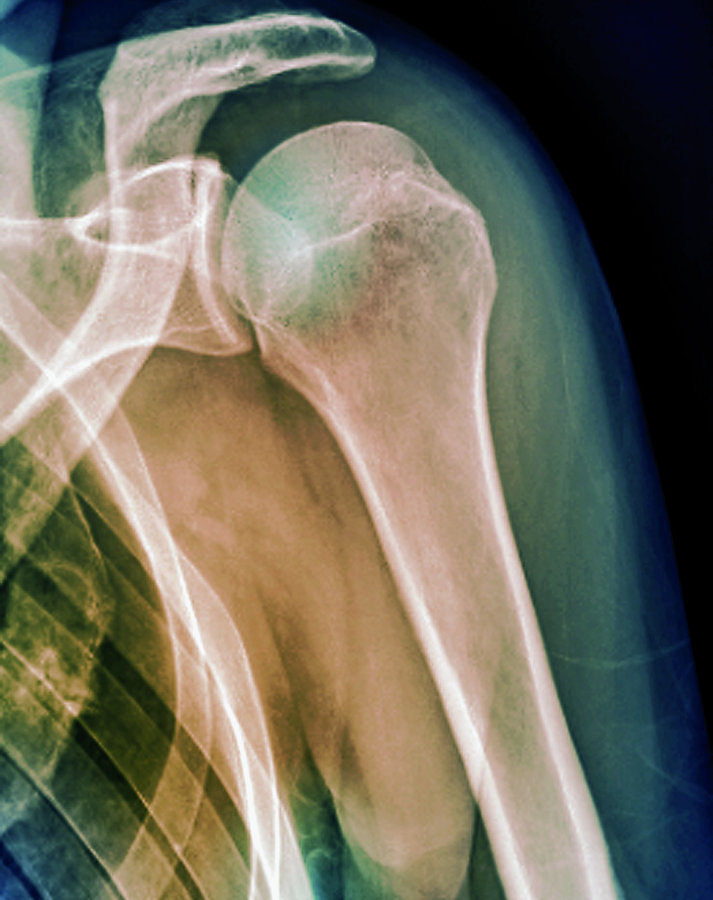

Mit einem Anteil von mehr als 95 % dominiert die anteriore Dislokation. In der Untersuchung fällt eine asymmetrische Schulterkontur mit prominentem Akromion und anteroinferior tastbarem Humeruskopf auf. Verdachtsdiagnose, Richtung der Dislokation und Begleitfrakturen der Tuberositas major lassen sich im Röntgenbild sichern (anterior-posteriore und skapulare Aufnahme).